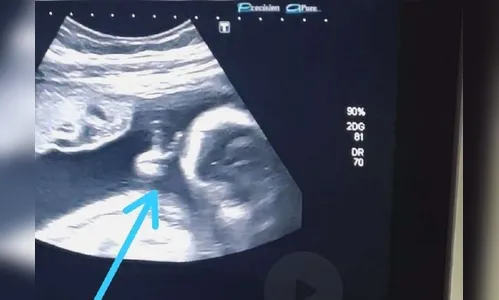

Ao acompanhar o exame de ultrassonografia de sexto mês do primeiro filho, o futuro pai viu o filho fazendo o ‘V de vitória’ com a mãozinha, dentro do útero e ficou chocado com a cena.

“Até a médica falou: ‘olha, ele fez o sinalzinho de vitória com a mão’. Eu fiquei sem acreditar”, contou.